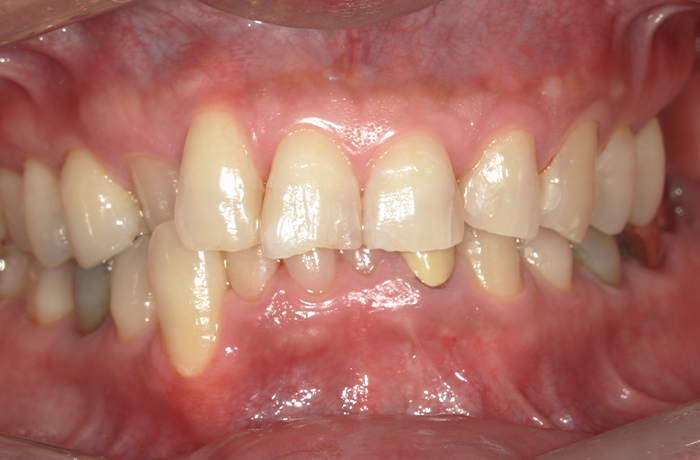

治療前

口腔内写真とレントゲン写真

左上6・7番欠損部は骨吸収が進行し、上顎洞底までの残存骨高径は5mm未満でした。

咬合支持が失われ、対合歯の挺出傾向がありました。